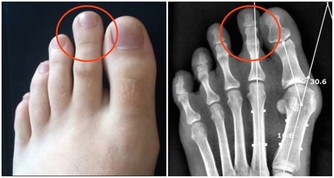

你手上是否有一顆顆亮晶晶的散在的小水皰,不癢不痛,每年定期反覆發作?

且水皰多半多夏季加重,冬季自愈?

如果是,你可能得了汗皰疹!

醫學認為,汗皰疹是濕疹的一種,是一種對稱性的、複發性的、多發生在手掌的水皰性疾病。汗皰疹發病有以下特點:

1、常夏季加重,入冬自愈,每年定期反覆發作;

2、水皰為位於表皮深處的小水皰,米粒大小,半球形,略高於皮表,分散或成群發生在手上;

3、內含清澈漿液,發亮,偶爾可變渾濁;

4、小水泡多不自行破裂,破裂后可見圓領狀脫皮;

5、一般無瘙癢、疼痛等異常感覺。